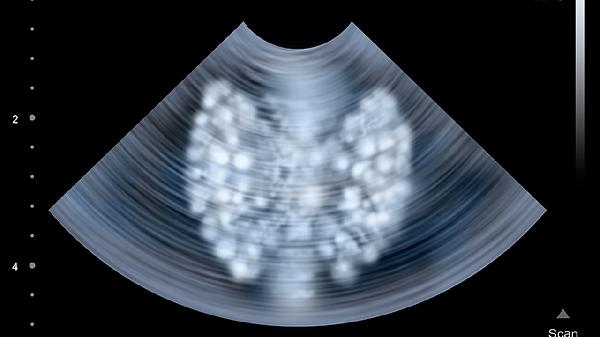

二维超声联合多普勒技术可评估心脏瓣膜功能、心肌运动及心包状况,测量射血分数是心功能的核心指标。先天性心脏病筛查能发现室间隔缺损等结构异常,心肌缺血区域表现为节段性运动减弱,需结合负荷试验进一步确诊。